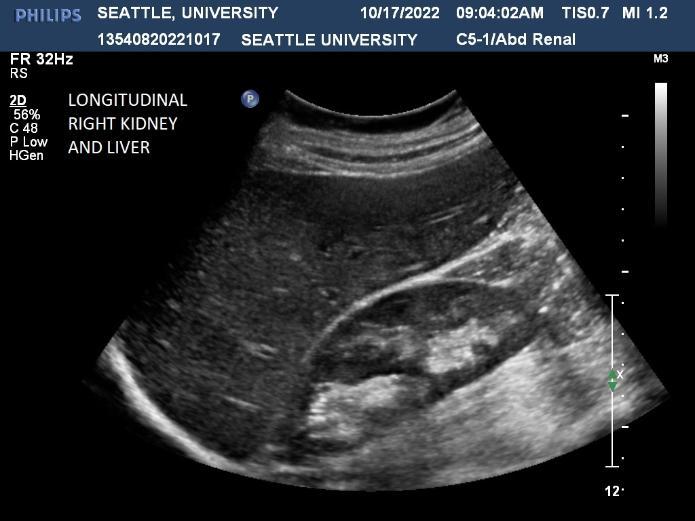

Ultrasound is a non-invasive diagnostic tool that uses high-frequency sound waves to propagate images of organs and tissues within the body. The Diagnostic Ultrasound program at Seattle University offers three distinctive track specializations in General (abdomen extended, OB/GYN) Vascular and Cardiac sonography.